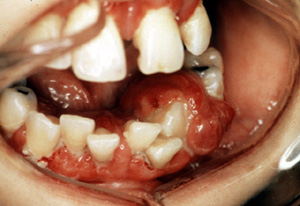

Aquí hay un ejemplo típico de  granuloma piógeno vascular, focalmente ulcerado. Éstos son generalmente asociados con algún tipo de irritación local; en este caso es probablemente el aparato ortodóntico. Por el color usted puede ver que la lesión es notablemente vascular y está casi exclusivamente compuesto de tejido de granulación.